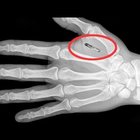

Swedish company Epicenter were in the news this week - first company to microchip their employees for efficiency gains. The inevitable future, or the mark of Cain? Maybe both, maybe neither. Futurist and humanist Gerd Leonhard provides insight into where we’re headed.